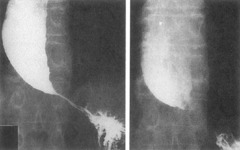

colorectal carcinoma found anywhere from the cecum to the rectum. most start out as a polyp. has an apple core radiographic appearance

colon cancer

Back